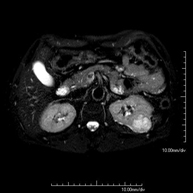

RM de RonyonsProva diagnòstica no invasiva que consisteix en l'obtenció d'imatges d'alta definició anatòmica d'ambdós ronyons mitjançant l'ús d'un camp electromagnètic i ones de ràdio (amb un emissor i un receptor). No utilitza radiació ionitzant. Es realitza per estudiar qualsevol lesió localitzada en ambdós ronyons. Normalment es requereix l'ús de contrast paramagnètic (Gadolini) per caracteritzar les lesions.